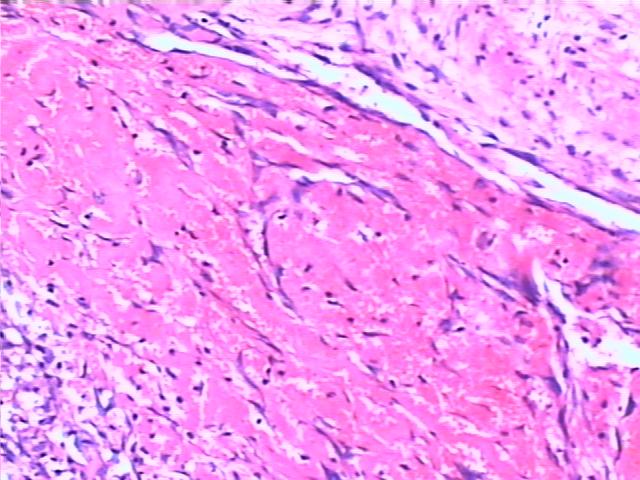

血栓的机化与再通 organization and recanalization of thrombus

1.血管腔内可见血栓与管壁紧密相连

2.血栓与血管壁相连处可见较多毛细血管、成纤维细胞、纤维细胞(机化)

3.血栓内散在大小不等的不规则腔隙,其中大的腔隙内被覆内皮细胞,内含红细胞(再通)。